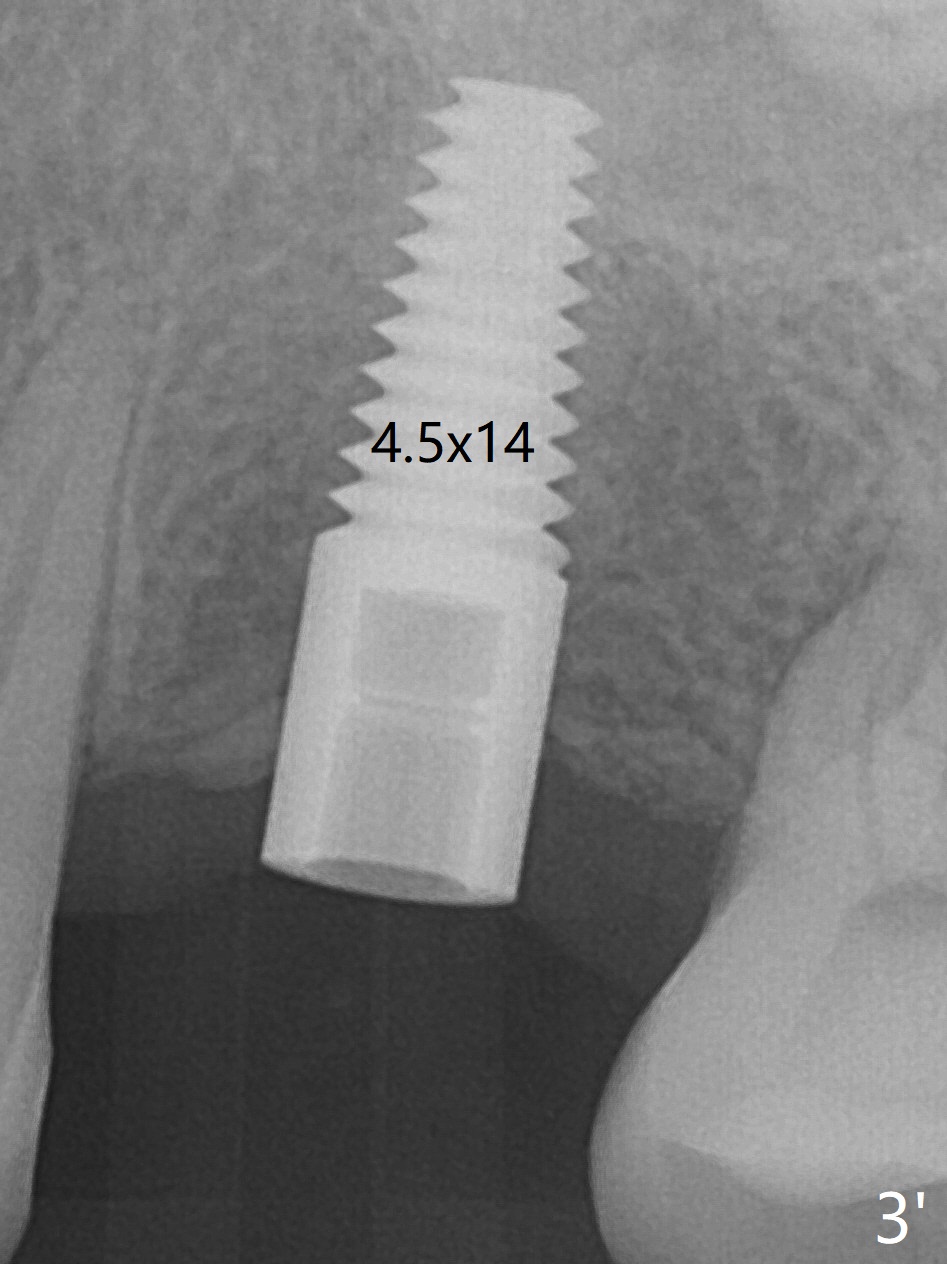

Immediately preop reanalysis of CT shows that there may be palatal thread exposure at #14 when a 4.5x14 mm tissue-level implant is placed equigingival (Fig.1,2). After sinus lift with IS 4x10 mm dummy implant with guide, the tissue-level tap and implant placed free hand look deep (Fig.3,3'). CT reveals possible 3 palatal threads exposed (Fig.4,5 arrowheads), which is associated with change in trajectory due to the palatal shift of the apex of the implant (arrow), as compared to the design of the bone-level implant (Fig.6). When there is a slope in the ridge and/or sinus floor, do not shift implants and use the guide for implant placement. If switching is necessary, use a final drill without underprep (Fig.7 red) through the sinus floor after sinus lift to avoid apical implant deviation. To fix the palatal thread exposure, palatal flap is raised. In fact the implant has to be removed for the incision. When the implant is re-placed deeper by ~ 1mm, there is a thread exposed. Bone graft is placed with collagen membrane. As a 4.5x3 mm abutment is placed, the implant is found to be unstable. Periodontal dressing is applied. In fact the implant exfoliates with the abutment 4.5 months postop (Fig.8). Bone graft seems to be necessary (sticky bone). Tissue level implant should be avoided for patient with poor oral hygiene. Return to Upper Molar Immediate Implant, Trajectory II 3 Xin Wei, DDS, PhD, MS 1st edition 08/30/2019, last revision 05/18/2020